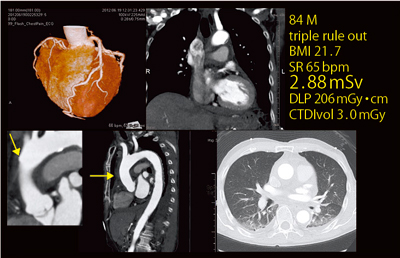

●症例5:血栓閉塞型上行大動脈解離

84歳,男性。胸痛のtriple rule out症例で心拍が安定していたため,Flash Chest Painで撮影した(図7)。冠動脈もきれいに描出されており,血栓閉塞型上行大動脈解離の状態も,エントリーを認めることができた。実効線量は2.88mSvと,非常に低被ばくであった。

図7 症例5:血栓閉塞型上行大動脈解離(Flash Chest Pain)